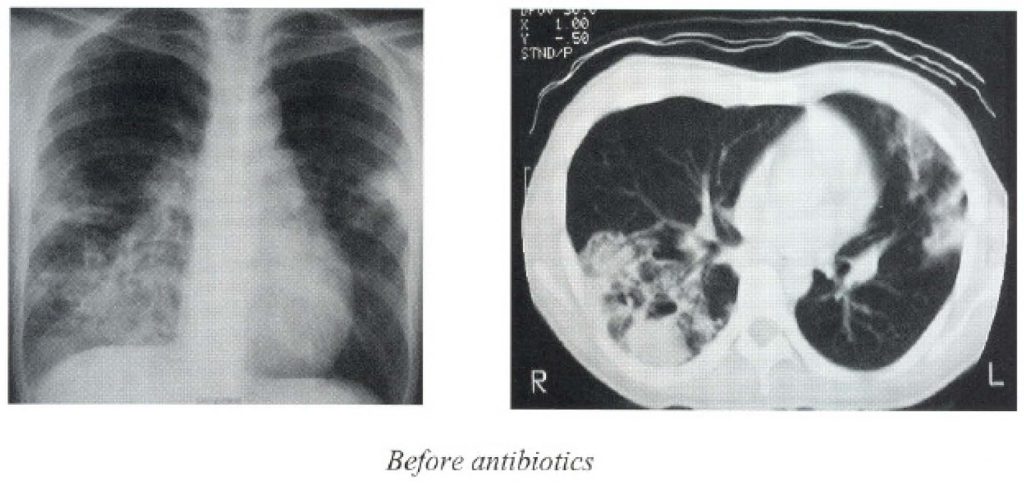

- Chest X-ray (CXR) revealed right lower lobe pneumonia and abscesses.

She received multiple courses of antibiotics including imipenem, metronidazole, Ampicillin/sulbactam, Ciprofloxacin, and even anti-TB medication for one week. However, there was no clinical or radiological improvement.

On arriving to Queen Mary Hospital, the patient had low grade fever. Otherwise, she was reasonably stable with blood pressure of 108/65 mmHg, pulse 104 bpm. There was no palpable lymph node. Chest examination revealed pleural effusion and crepitation over the right lower zone. Examination of other systems was unremarkable. CXR showed multiple cavitations and fluid levels over the right lower lobe. There was also consolidation over the left middle zone as well.

The oral medication (doxycycline and TMP-SMZ) was maintained for 6 months. The ensuing CXR showed resolving cavitating pneumonia with residual right lower lobe haziness, see figure. The serial pseudomallei titer remained at 1:40 on subsequent follow up.